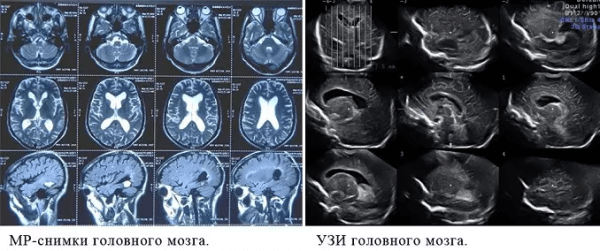

Что показывает МРТ

Магнитно-резонансная томография или МРТ - это сфокусированный метод, который проводит очень детальное обследование. Диагностическая точность МРТ превышает УЗИ и во многих случаях КТ, за исключением сканирования полых органов (легких, желудка, кишечника) и костей. МРТ является золотым стандартом диагностики:

Принцип работы МРТ основан на эффекте ядерного магнитного резонанса. МР томограф в своей конструкции имеет мощный магнит, который создает магнитное поле, и датчик, который подает радиочастотные сигналы. В такой ситуации протоны атомов водорода начинают колебательные движения, выделяя при этом импульсы. Их улавливает компьютер томографа и преобразовывает в трехмерные изображения. Чем больше воды содержится в клетках ткани, тем детальней получается ее изображение. Поэтому на МРТ хорошо отображаются органы с большим содержанием воды: МРТ головного мозга, МРТ спинного мозга, МРТ глазных орбит, МРТ органов малого таза, МРТ позвоночника, МРТ суставов, и плохо визуализируются органы с большим содержанием воздуха МРТ органов грудной клетки или кости.

Что покажет УЗИ

Ультразвуковое исследование или УЗИ - это широко распространенный вид обследования, активно применяемый в диагностических центрах СПб. В ходе данной процедуры диагностика проводится с помощью ультразвуковых волн. Проходя через границы тканей различной плотности, ультразвук по-разному отражается от них. Ультразвуковая установка имеет датчик, который посылает ультразвуковой сигнал, а затем фиксирует ответ и переводит его в графическое изображение. Таким способом врачи могут хорошо обследовать:

К сожалению, серьезным препятствием для ультразвука являются кости, через которые сигнал пробиться не может. Поэтому малоинформативным является

- УЗИ головного мозга

- УЗИ сердца

- УЗИ органов средостения

- УЗИ позвоночника.

Есть некоторые органы, обследование которых рекомендуют начинать с проведения МРТ. В частности, речь идет о головного мозге. С помощью УЗИ оценить его строение у взрослых очень проблематично, т. к. со всех сторон мозг заключен в череп, который практически не пропускает ультразвуковых волн. Для МРТ это не является препятствием.